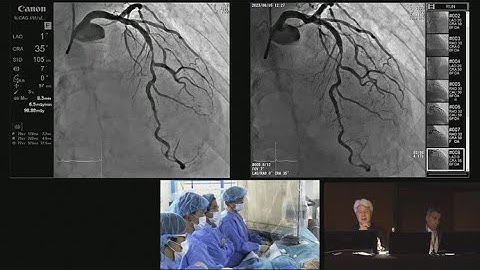

Fluoroscopic Image Quality